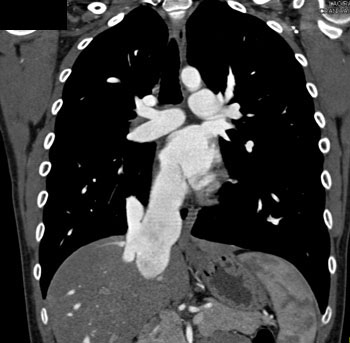

|  | Question 4: 20 year old male with a history of mitral valve prolapse and increasing exertional dyspnea and palpitations. What’s the diagnosis? |